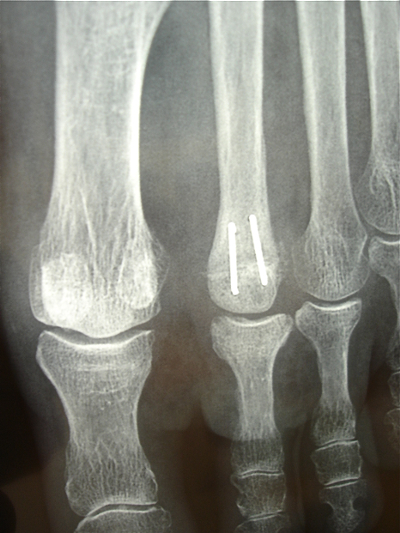

La fixation de fait par un fil trans-osseux en cadre ou deux agrafes métalliques fines placées à la face dorsale.

Exemple sur une ostéonécrose de la 2e tête métatarsienne G:

la tête est aplatie et carrée mais sans arthrose sur le versant phalangien.